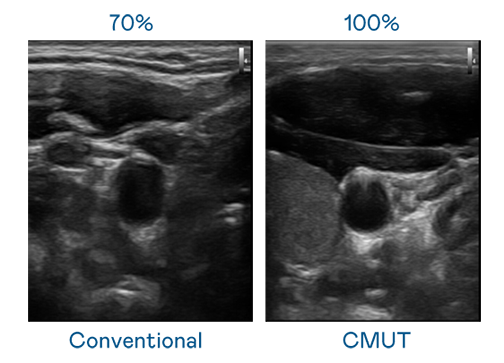

CMUT 技术是一种用电容式微机电元件来产生超音波讯号的技术。与传统 PZT 压电式技术相比,CMUT 频宽增加 30%,更宽频的超音波讯号让影像解析度大幅提升,是实现高影像品质医疗超音波扫描、促进精准医疗发展的关键技术。

超音波影像的解析度高低,首先取决于探头能发出的讯号频宽。云顶集团3118 CMUT 可提供高清晰的超音波讯号,提供高频宽、高灵敏度、影像纹理细节更高的超音波影像,协助医护人员缩短影像判读时间及利用精准的医疗影像进行诊断。